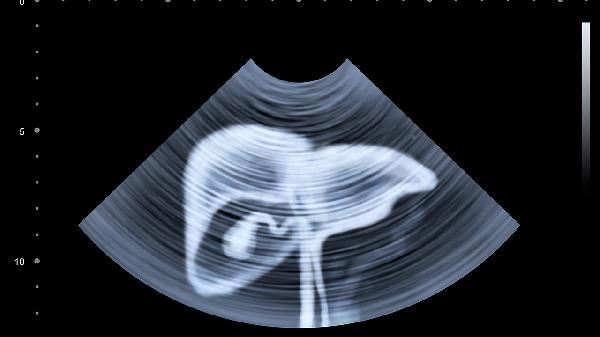

囊肿蒂部旋转导致缺血性疼痛,表现为突发性左下腹撕裂样痛,伴恶心呕吐。超声显示囊肿血流信号消失。需急诊行腹腔镜下囊肿切除术,避免卵巢坏死。